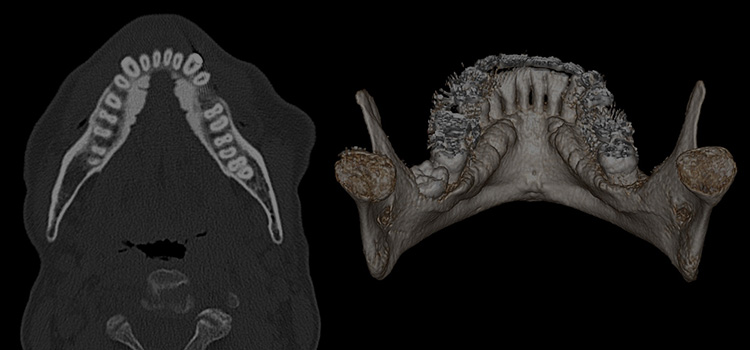

Mandibular Tori | Radiology Reference Article | Radiopaedia.org

Mandibular tori | Radiology Reference Article | Radiopaedia.org radiopaedia.org

mandibular tori torus radiopaedia radiology

Figure 1 From Mandibular Tori. | Semantic Scholar

Figure 1 from Mandibular tori. | Semantic Scholar www.semanticscholar.org

tori mandibular